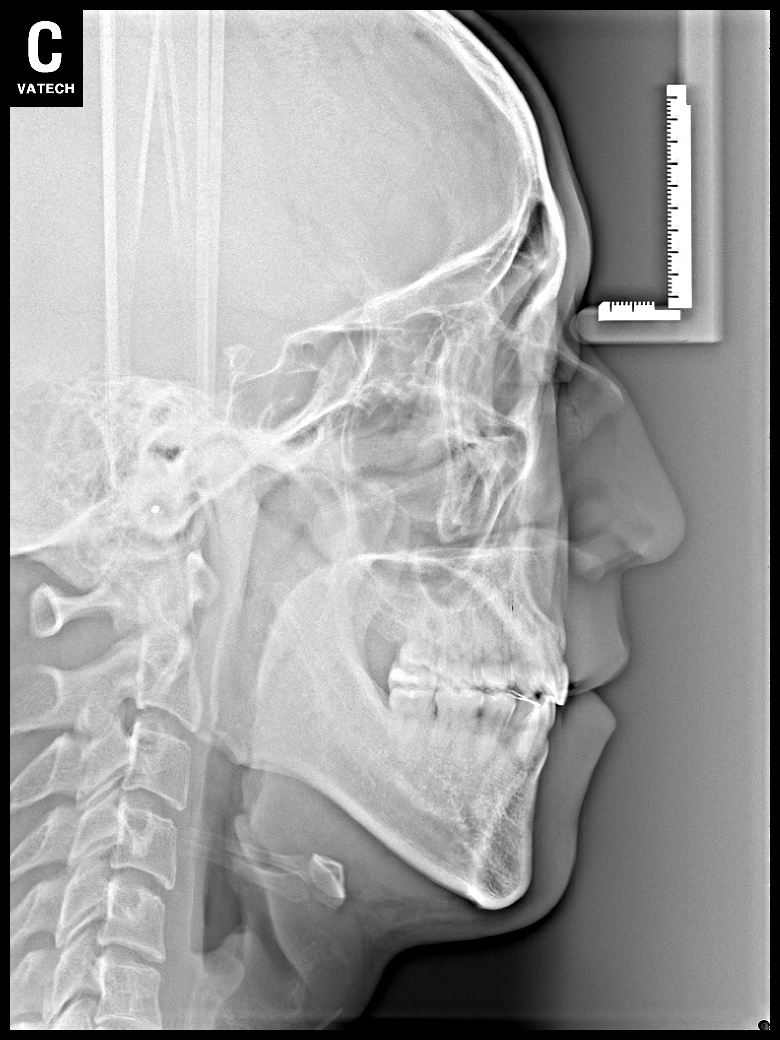

치료 전 사진입니다.